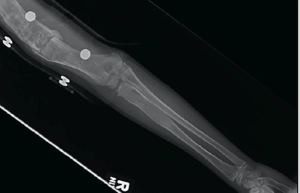

The patient, an 8-year-old male who recently immigrated to the United States from El Salvador, initially presented to the emergency department (ED) for a cough. The next day, he went to the general pediatrics clinic for follow-up and was noted to have a significant history of recurrent fractures.